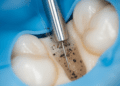

Um dos aspectos mais importantes é o nível de detalhe radiográfico da imagem. Altos níveis de detalhe permitem que professionals identifiquem pequenas fraturas, cáries incipientes e outras anomalias que poderiam passar despercebidas em imagens de menor qualidade. Para isso, é crucial que a tecnologia utilizada seja de ponta e que a técnica de exposição seja ajustada corretamente.

Outro fator vital é a densidade e o contraste da radiografia. A densidade refere-se ao grau de escuridão da imagem, enquanto o contraste se refere à diferença entre áreas claras e escuras. Para um diagnóstico eficaz, a densidade deve ser média, o que permite uma visualização clara dos tecidos moles e duros. Uma imagem com contraste adequado realça os detalhes necessários para a análise, evitando confusões que podem surgir de imagens excessivamente claras ou escuras.

Para determinar se uma radiografia é de qualidade, os profissionais podem avaliar alguns aspectos técnicos. Verifique se a imagem é livre de artefatos, que podem distorcer a visualização. Imagens nítidas, com definição clara das bordas, são essenciais. Além disso, a localização correta das estruturas anatômicas é crucial. Por exemplo, elementos como raízes dentárias e seios maxilares devem aparecer de forma adequada. Uma radiografia bem posicionada irá contribuir para um diagnóstico mais assertivo.